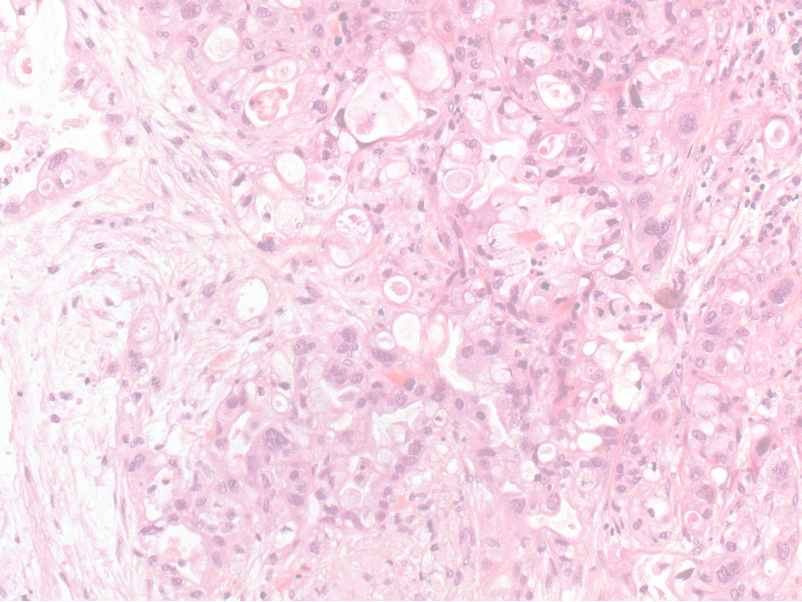

Die Pathologie

Die Pathologie (von altgriechisch πάθος páthos, deutsch ‚Krankheit, Leiden‘, und λόγος lógos, deutsch ‚Lehre‘, also „Lehre von den Leiden“) ist historisch aus der allgemeinen medizinischen Forschung und der Anatomie hervorgegangen. Mit der Beschreibung der Zellularpathologie durch Rudolph Virchow im 19. Jahrhundert wurde der Grundstein der heutigen Pathologie gelegt, die sich primär mit der Untersuchung krankhafter Veränderungen von Zellen und Geweben befasst. In ihrer heutigen Form ist die Pathologie essenzieller Lotse in der Therapie verschiedenster Erkrankungen. Kurz gesagt: Ohne Diagnose keine Therapie.

Dabei untersucht die klinische Pathologie:

- Gewebeproben und Flüssigkeiten von Patient:innen nahezu aller klinischen Fachrichtungen.

- stellt Diagnosen.

- klassifiziert Erkrankungen.

- identifiziert Therapieziele und ermöglicht somit die korrekte und in der jeweiligen Situation indizierte individuelle Behandlung.